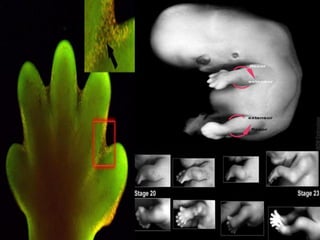

La formación del miembro

comienza como un esbozo de

la extremidad. El factor de

crecimiento de fibroblastos

(FGF) induce la formación de

un organizador llamado cresta

ectodérmica apical, que guía el

posterior desarrollo y controla

la muerte celular. La apoptosis

muerte celular programada

que es necesaria para eliminar

las membranas interdigitales.

La muerte celular programada elimina la

membrana interdigital entre los dedos y

las articulaciones.

Lo miembros se generan a partir de un esbozo por procesos

de diferenciación y crecimiento en los que intervienen

distintos tipos de genes:

• Los Homebox

• Genes de la familia del factor de crecimiento

fibroblastico

Así se generan los 3 ejes de un miembro:

• Un eje anteroposterior con una parte anterior

correspondiente a la zona donde estará el pulgar y una

parte posterior en donde estará el meñique.

• un eje proximal (donde estará el hombro) y uno distal

(donde se localizará la mano).

• Un eje dorso ventral.

En el desarrollo de los esbozos es importante la actividad del

repliegue apical ectodérmico, además aquí funcionan los genes del

factor de crecimiento fiblobastico y la zona de actividad polarizante

donde tiene actividad la vía de señalización, también es importante la

zona de progresión de manera que al final se llega a esbozar un

miembro completo con los dedos, la región cubital y la región radial